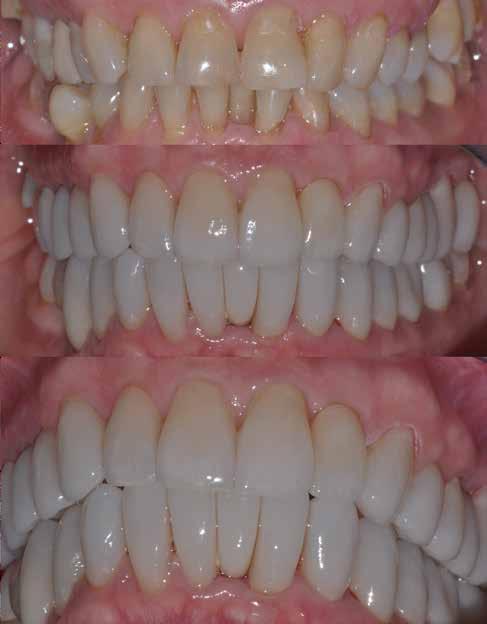

A fogászati kezelések során manapság már nem kizárólag az esztétikai megjelenés helyreállítására törekszünk. Sokszor a kedvezőtlen esztétikai megjelenés hátterében álló okok következményes módon a fogazat funkcionális működését is károsítják, így a kezelések során ezeknek a helyreállításával is foglalkoznunk kell. A különböző funkcionális és esztétikai diszkrepanciák kezelésére számtalan módszer létezik, ám ezen fogászati beavatkozások mindegyikében közös, hogy a kivitelezésük során nagyon szoros együttműködésre van szükség a kezelést végző fogorvos és a munkáját segítő fogtechnikus között. Az alábbi esetbemutatás során egy fiatal hölgypáciens fogazatának héjak alkalmazásával történő esztétikai és funkcionális rehabilitációját szeretnénk ismertetni.

A 19 éves hölgypáciens azzal a kéréssel jelentkezett a rendelőnkbe, hogy szebb fogakat szeretne. Az első konzultáció alkalmával megkérdeztük, hogy mi zavarja leginkább a fogazatának jelenlegi megjelenésében, valamint azt is megbeszéltük vele, hogy milyen végeredmény elérése esetén lenne maradéktalanul elégedett. Ebben az esetben a kezelési célokat az alábbiakban határoztuk meg:

A páciens fogazata esztétikai megjelenésének és funkcionális működésének a lehető legtöbb, saját foganyag megtartása mellett történő helyreállítása (1. és 3. ábra).

A lehető legideálisabb esztétikai végeredmény elérése érdekében néhány esetben a fogak alakjának módosítá -

A kezelés megtervezése során kifejezett jelentősége van annak, hogy jó kommunikáció legyen a páciens, a fogorvos és a fogtechnikus között. A páciens leendő fogazatának természetes megjelenését a kezelésben részt vevő team szakmai felkészültsége, gyakorlati tapasztalata és a kezelés sikerességének irányába történő elkötelezettsége biztosítja. A beavatkozások megkezdése előtt megtörtént a páciens anamnézisének a felvétele, valamint a klinikai kivizsgálását is elvégeztük. Ezt követően lenyomatokat készítettünk a kiindulási állapotról, majd a kiindulási helyzetet extra- és intraorális fotók segítségével is rögzítettük (13. a-c. ábra).

A kezeléstervezés egyik legfontosabb lépése a mock-up elkészítése. A mock-up alapjául szolgáló wax-up-ot (felviaszolás) is ugyanolyan részletességgel kell a fogtechnikusnak elkészíteni, mintha azok már a végleges fogpótlások alapjául szolgáló mintázatok lennének. A mock-upnak nagyon pontosan kell illeszkednie, valamint a tervezett fogpótlás meg-

jelenését is rendkívül élethűen kell reprezentálnia. Ahhoz, hogy a páciens mock-uppal kapcsolatos első benyomásai kedvezőek legyenek, a mock-up színének a páciens „szemfehérjének” színével meg kell egyeznie. A kezelési cél páciens által történő elfogadása és a tervezett eredménnyel kapcsolatos „wow-effektus” kialakulása nagyban függ a páciensben az első megtekintés során kialakult első benyomásoktól.

Az eddigi tapasztalataink szerint a páciensek jelentős többsége egyértelműen kifejezi az elégedettségét, ha a mock-up megfelel az eredeti elképzeléseiknek. A bemutatásra kerülő esetben is ez történt. A tervezett végeredmény megtekintését követően a páciens azonnal kérte az általunk javasolt kezelési tervben ismertetett beavatkozások elvégzését. A héjak alapanyagául az Ivoclar Vivadent által gyártott A1-es színű Telio CS kerámiát javasoltuk. Az anyagválasztás hátterében az állt, hogy ez az anyag nagy keménységgel rendelkezik, valamint az, hogy a felszínét nagy simaságúra lehet polírozni. A páciens rendkívül fiatal életkora is azt a terápiás koncepciót erősítette, hogy a kezelés során lehetőség szerint kizárólag non-invazív beavatkozásokat alkalmazzunk.

A páciens már kezdetben is rendkívüli érdeklődést mutatott a preparálást nem igénylő (non-prep), héjakkal történő ellátással kapcsolatban. Ennek a terápiás modalitásnak az előnyei közé tartozik, hogy a fogakat egyáltalán nem, vagy csak minimál invazív módon kell preparálni, nincs szükség ideiglenes héjak készítésére, a héjak alapanyagául szolgáló kerámia nem hajlamos az elszíneződésre, nem jellemző a beavatkozások elvégzését követően jelentkező posztoperatív szenzitivitás, valamint hogy ezzel a módszerrel rendkívül kedvező esztétikai végeredményt lehet elérni. A fenti előnyök rendkívül meggyőzően hatottak a páciensre. A döntése során azt is figyelembe vette, hogy amennyiben ezeket a viszonylag költséges restaurátumokat választja, akkor ez a kezelés végösszegét is jelentős mértékben befolyásolja.

A kezelés során az jelentette a legnagyobb kihívást, hogy a héjakkal ellátott fogak élethűen utánozzák a természetes fogazat megjelenését. A fogpótlás színének, valamint a restaurátumok felszíni textúrájának és alakjának harmonikusan kell a páciens arcesztétikájához és karakteréhez illeszkednie.

A tényleges protetikai ellátás megkezdése előtt a páciens mosolygás közben látható fogait otthoni fogfehérítés keretei között a kérésének megfelelő A1-es fogszín eléréséig fehérítettük. A fehérítés során a későbbiekben héjakkal ellátásra kerülő fogak színén nem változtattunk. A fogak előkészítése részeként csupán a két felső nagymetsző (1.1,2.1) incizális élét kellett kismértékben redukálni. A többi felső front fog (1.3,1.2,2.2,2.3) nem került preparálásra.